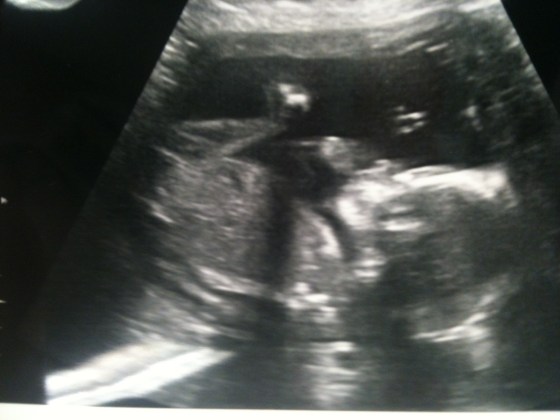

I was excited to get another glimpse of you! We can’t wait to meet you……but we know you need to stay in there another 18 weeks or so until you are ready to come out!